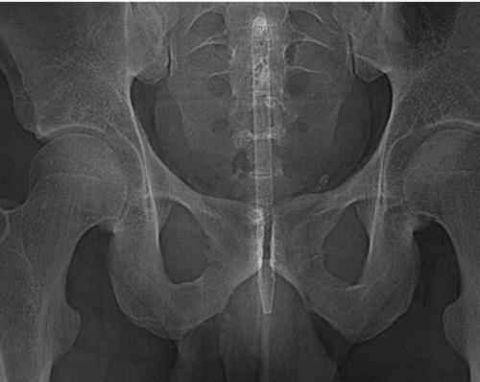

一支圆珠笔,话说这么细会舒服么?